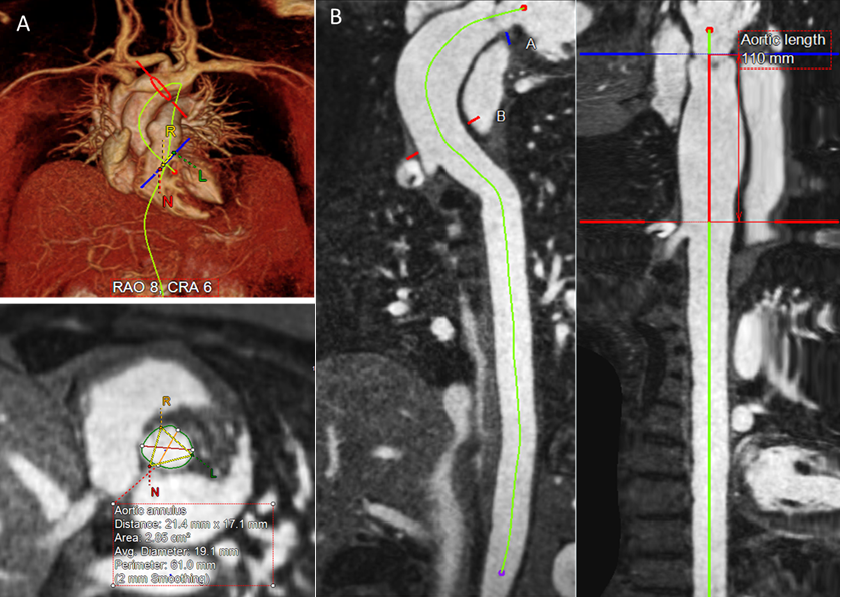

Figure 1. Semi-automated centerline post-processing of contrast enhanced MRA images. The aortic annulus is defined by placing seeds at the insertion of the right, left and non-coronary cusp (A). Using the straightened multi-planar reformats, the ascending aortic length is measured from the aortic annulus to innominate artery origin (B).